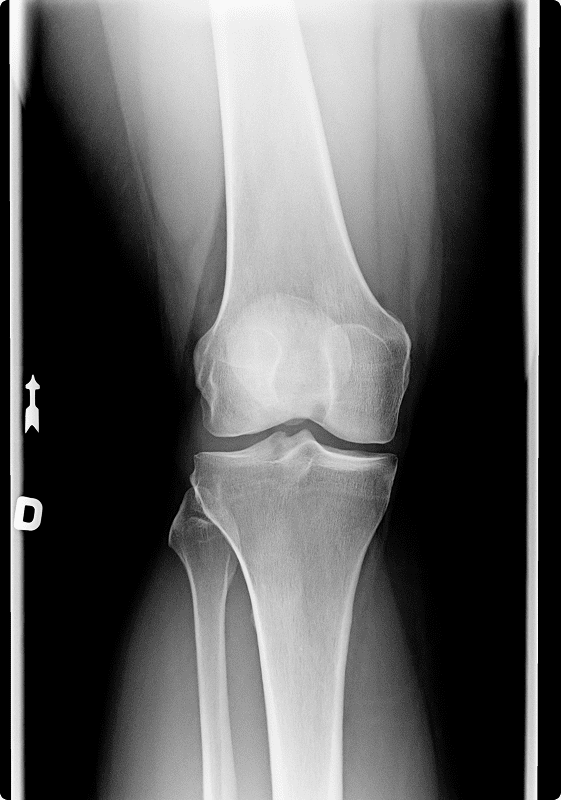

Initial evaluation includes a medical history and physical examination. X-rays are not often indicated. Examination includes provocative maneuver testing.